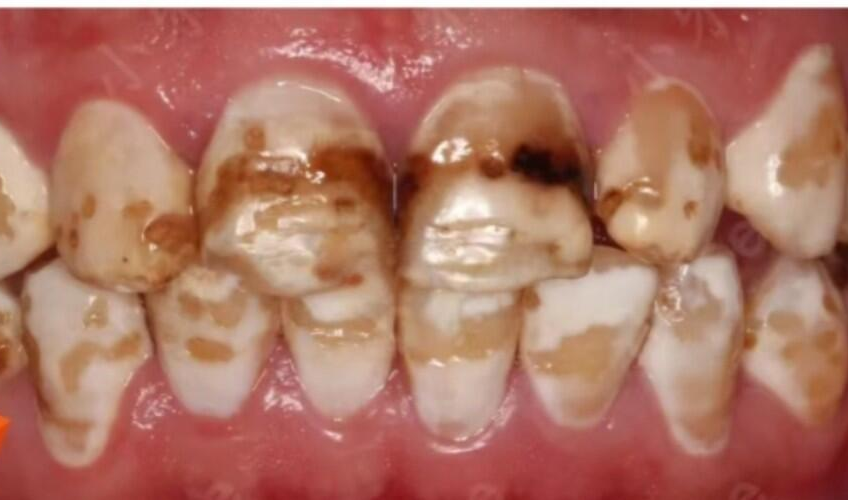

2.中度(着色型): 牙齿表面出现黄褐色或棕色的斑块,影响美观,但牙体形态没有明显缺损。

3.重度(缺损型): 除了严重的颜色改变,牙釉质还会出现凹凸不平的坑洼、缺损,甚至可能引发牙齿敏感。